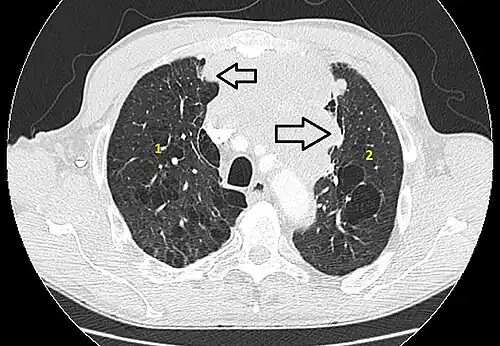

Les thymomes se présentent comme une masse bien définie du médiastin antérieur, proche du péricarde et dans un plan plus antérieur que les gros vaisseaux intrathoraciques (aorte ascendante et sa crosse, artère pulmonaire, veine cave supérieure). La masse peut être sphérique ou lobulée, mais présente un aspect homogène (plus rarement kystique) qui se réhausse après injection et peut contenir des calcifications[29].

Les critères scanographiques d'envahissement local doivent être recherchés car ils guideront le traitement. D'autre part, l'envahissement scanographique est corrélé au pronostic[30]. L'absence d'un liseré graisseux entre la masse et les vaisseaux, notamment l'aorte et la veine cave supérieure, est un signe d'envahissement local. L'ascension d'une coupole diaphragmatique, comme en radiographie thoracique, est un signe d'envahissement du nerf phrénique[31].

L'irrégularité des contours de la tumeur, ainsi que la présence de calcifications, de nécrose ou d'hémorragie intratumorale sont des signes de mauvais pronostic corrélés à des tumeurs plus agressives[32].

- Aspect scannographique

6 : sternum.- Scanner en fenêtre parenchymateuse, montrant un carcinome thymique envahissant les poumons (avec des lésions d'emphysème) au contact des deux poumons (1 : poumon droit ; 2 : poumon gauche) ;

flèches noires : zones suspectes d'envahissement.